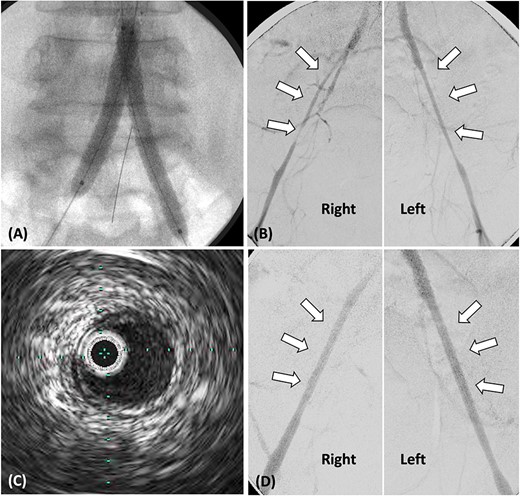

A 48-year-old man with a history of hypertension, dyslipidemia, and hyperuricemia presented with intermittent claudication for 50 m in both lower limbs. His body mass index (BMI) was 31.7 kg/m2. The patient’s right and left ankle-brachial index (ABI) values were 0.40 and 0.32, respectively. Contrast-enhanced computed tomography (CT) revealed complete bilateral common iliac artery (CIA) occlusion from the abdominal aorta at the inferior mesenteric artery (IMA) level (Fig. 1A). Furthermore, CT revealed bilateral EIA stenosis (right, 4.3 mm; left, 4.4 mm) without calcification or atheroma (Fig. 1A). He was diagnosed with AIOD with EIA stenosis, and was administered endovascular treatment because he was obese.

(A) Pre-operative contrast-enhanced CT reveals bilateral CIA occlusion from the abdominal aorta, with bilateral EIA stenosis, without calcification. (B) Contrast-enhanced CT 8 months post-surgery shows good bilateral EIA dilatation.

On post-operative day 2, the patient exhibited an ABI value of 0.99 in both lower limbs, recovered well, and was discharged. Eight months post-surgery, contrast-enhanced CT revealed no stenosis, and both EIA diameters improved (right: 8.3 mm, left: 7.5 mm) (Fig. 1B).